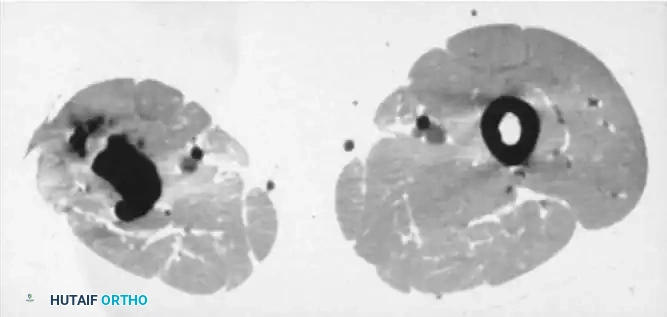

Image

Fig. 15-3 A and B, CT scans showing dense, isolated sequestra within the medullary canal, surrounded by a sclerotic involucrum.